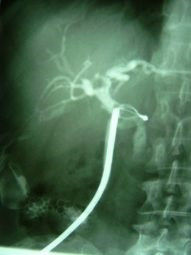

Litotripsia y extracción de cálculo de coledoco residual

Envíado por Dr. Carlos Miguel Zavaleta Consuegra